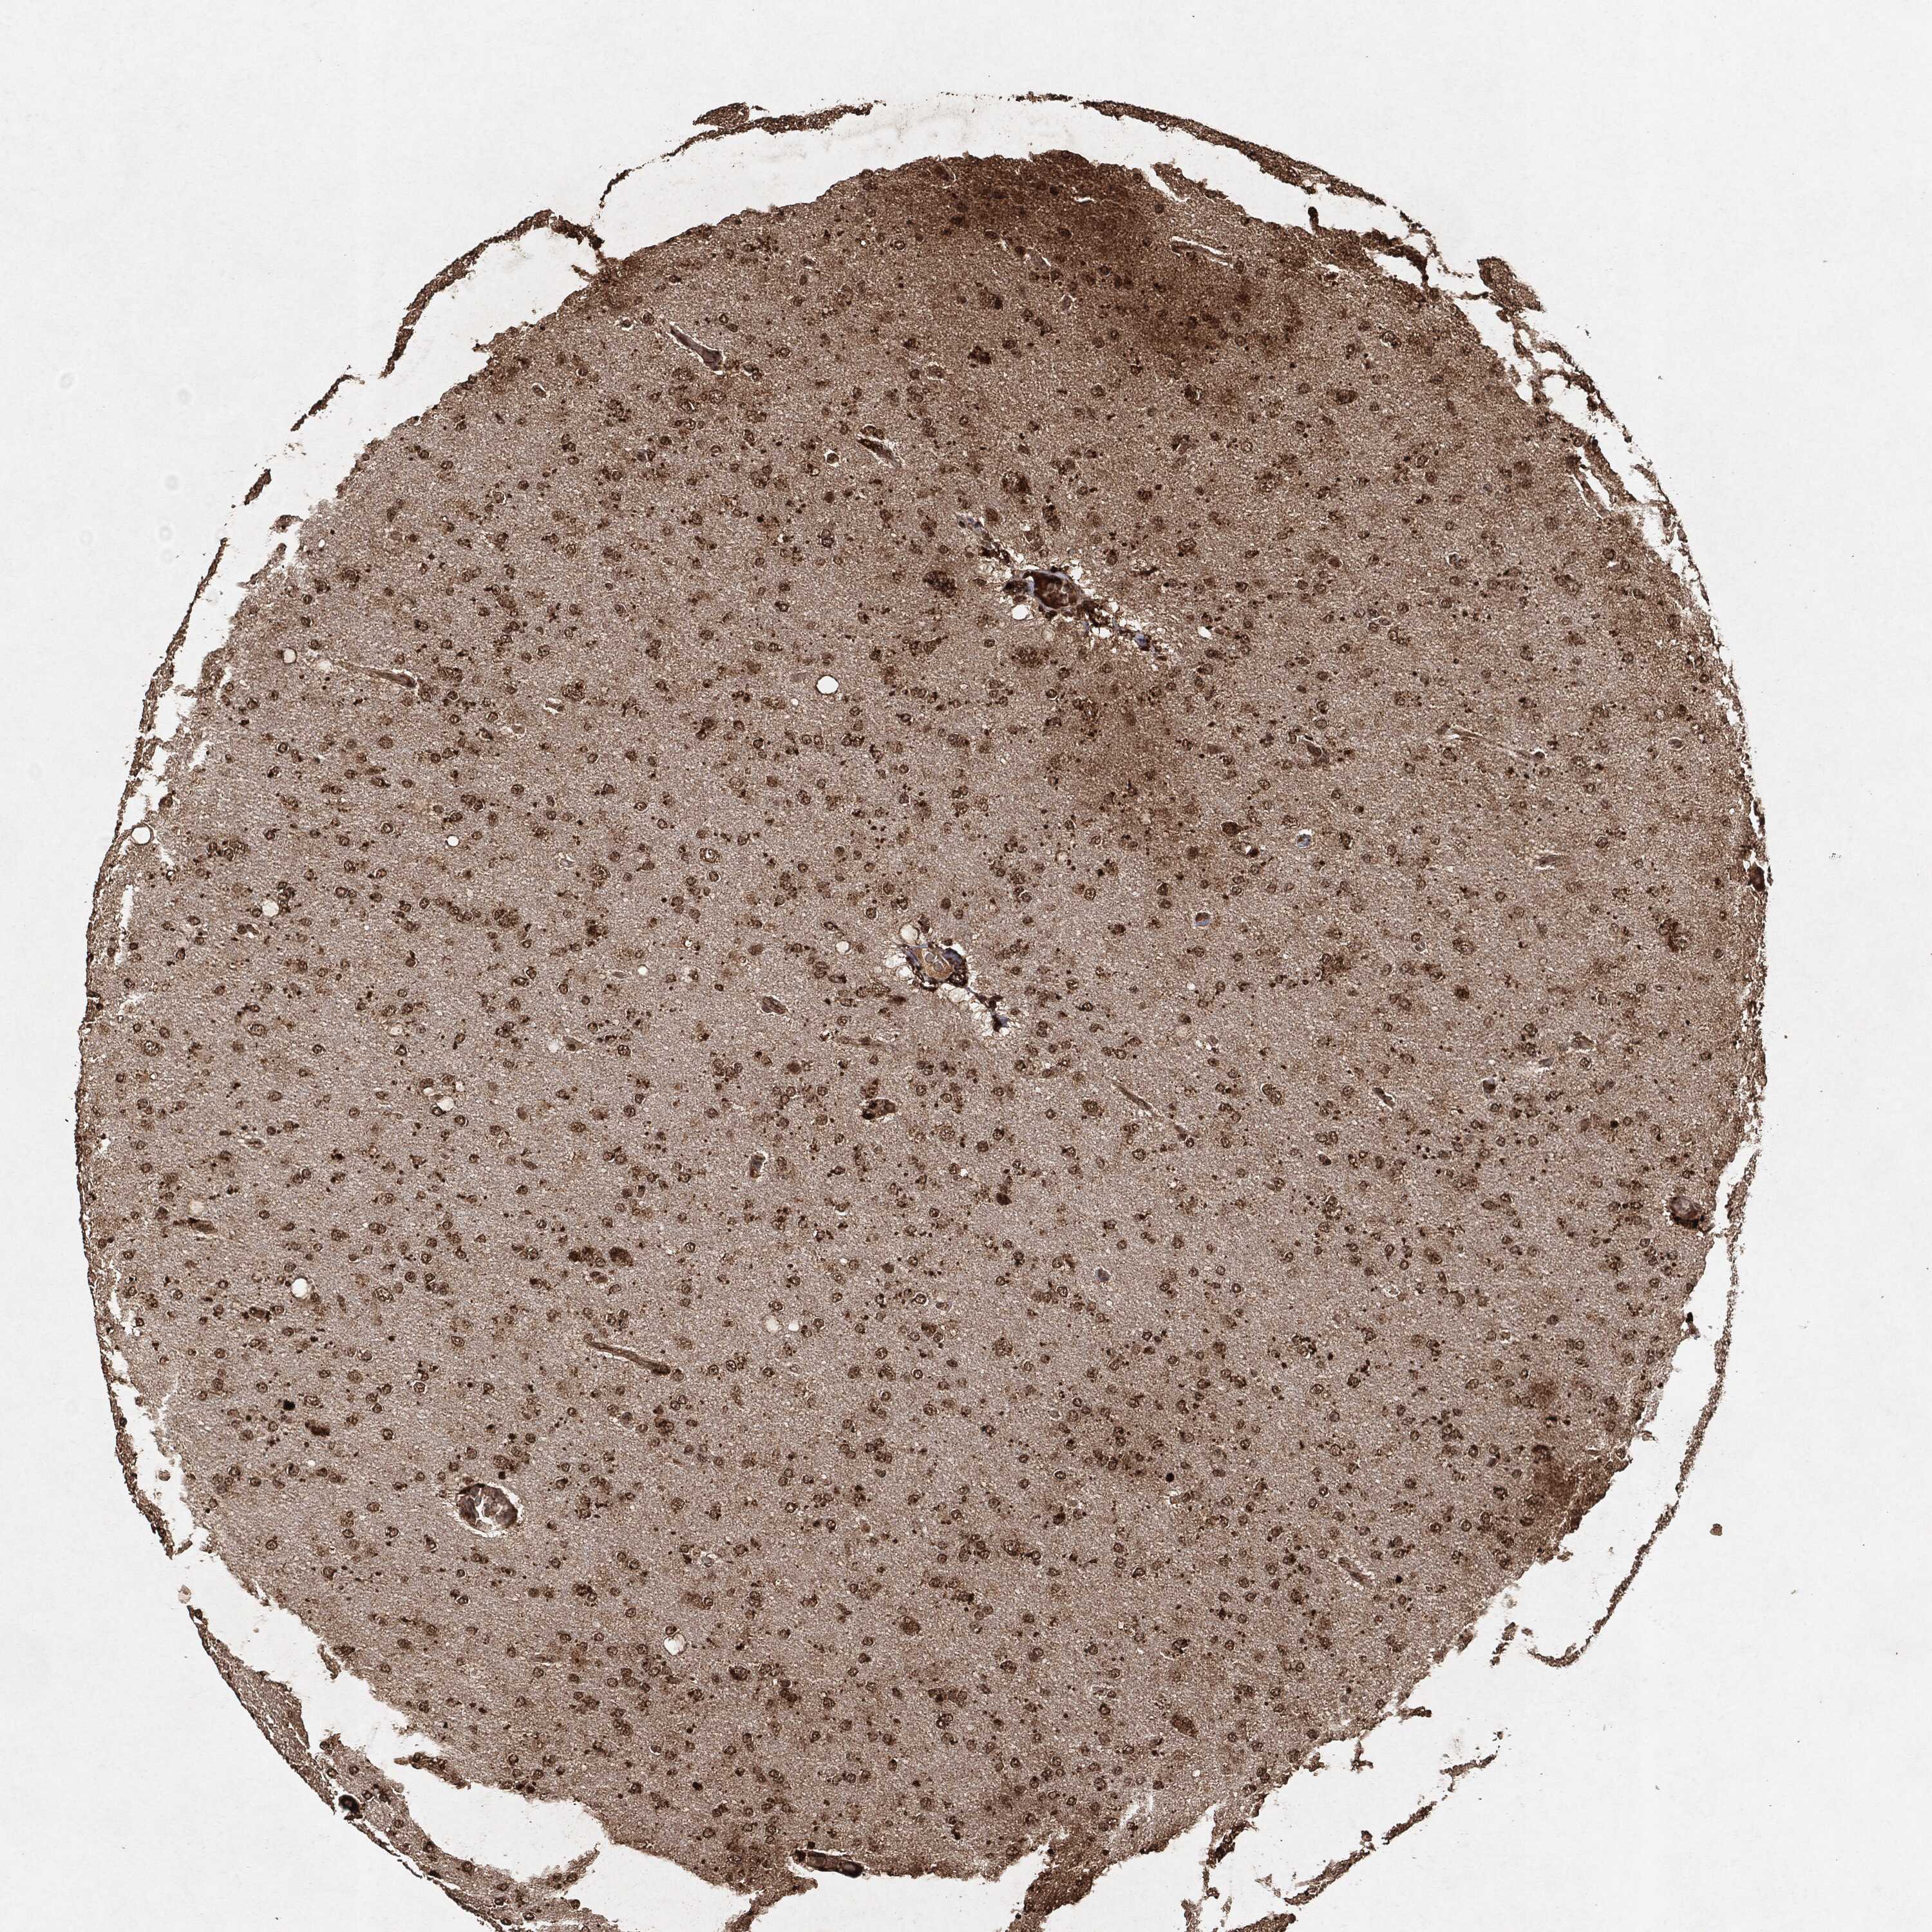

GLIOMA - Protein expressioni

A mouse-over function shows sample information and annotation data. Click on an image to view it in a full screen mode. Samples can be filtered based on level of antibody staining by selecting one or several of the following categories: high, medium, low and not detected. The assay and annotation is described here.

Note that samples used for immunohistochemistry by the Human Protein Atlas do not correspond to samples in the TCGA dataset.

Antibody stainingi

Antibody staining in the annotated cell types in the current human tissue is reported as not detected, low, medium, or high, based on conventional immunohistochemistry profiling in selected tissues. This score is based on the combination of the staining intensity and fraction of stained cells.

Each image is clickable and will lead to virtual microscopy that enables deeper exploration of all samples and also displays staining intensity scores, fraction scores and subcellular localization as well as patient and tissue information for each sample.

Glioma, malignant, High grade

Glioma, malignant, Low grade

Glioma, malignant, NOS